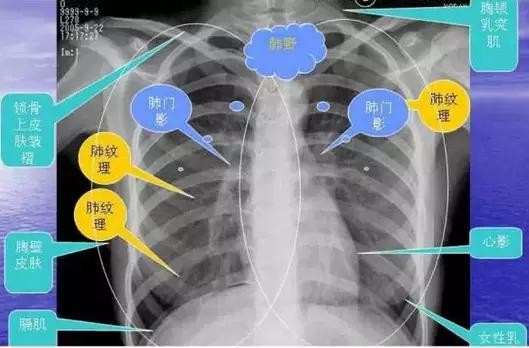

详尽的胸部CT影像示意图

胸部的CT是通过X线计算机体层摄影(CT)对胸部进行检查的一种方法。正常胸部CT层面较多,每一层面结构所表现的图像不同。下面是胸部CT图文示意图,可帮助临床医生详细了解CT结构。我们一起来看一下吧。